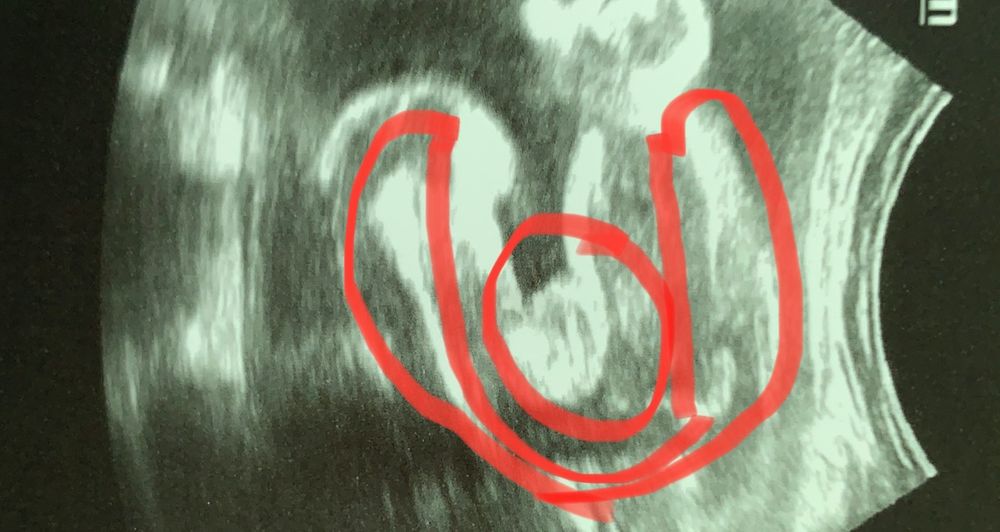

УЗИ 20 недель, пол ребенка

Может быть кто-то знает или имеет опыт - врач сказал, что это девочка, но позднее, пересматривая видео с других ракурсов, наткнулись на такое. Неужели половые губы могут быть такими продолговатыми? В общем, терзают сомнения :)